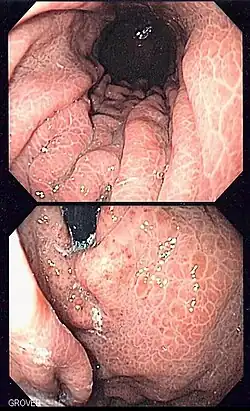

Image of portal hypertensive gastropathy seen on endoscopy of the stomach. The normally smooth mucosa of the stomach has developed a mosaic like appearance, that resembles snake-skin.

Portal hypertensive gastropathy refers to changes in the mucosa of the stomach in patients with portal hypertension; by far the most common cause of this is cirrhosis of the liver. These changes in the mucosa include friability of the mucosa and the presence of ectatic blood vessels at the surface. Patients with portal hypertensive gastropathy may experience bleeding from the stomach, which may uncommonly manifest itself in vomiting blood or melena; however, portal hypertension may cause several other more common sources of upper gastrointestinal bleeding, such as esophageal varices and gastric varices. On endoscopic evaluation of the stomach, this condition shows a characteristic mosaic or "snake-skin" appearance to the mucosa of the stomach.

The diagnosis of portal hypertensive gastropathy is usually made on endoscopy. The usual appearance of portal hypertensive gastropathy on endoscopy is a mosaic-like or reticular pattern in the mucosa. Red spots may or may not be present. The pattern is usually seen throughout the stomach.[2] A similar pattern can be seen with a related condition called gastric antral vascular ectasia (GAVE), or watermelon stomach. However, in GAVE, the ectatic blood vessels are more commonly found in the antrum or lower part of the stomach.[2]